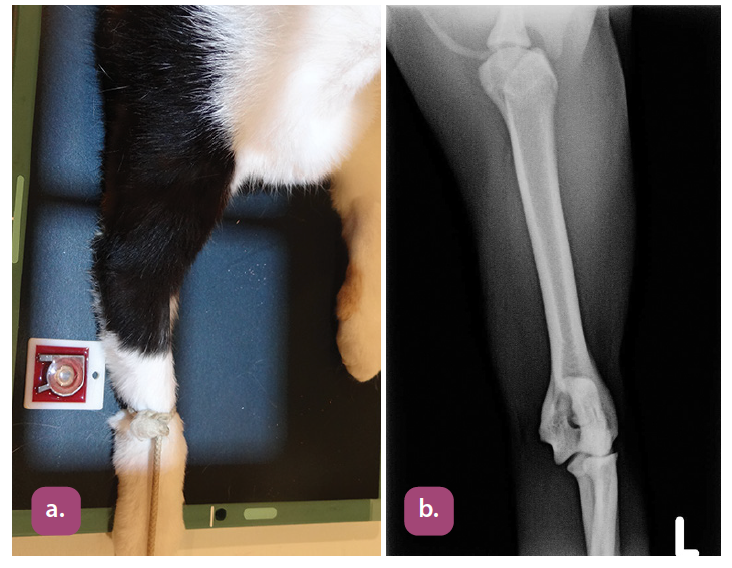

mediolateral projection of the radius and ulna

craniocaudal projection of the radius and ulna